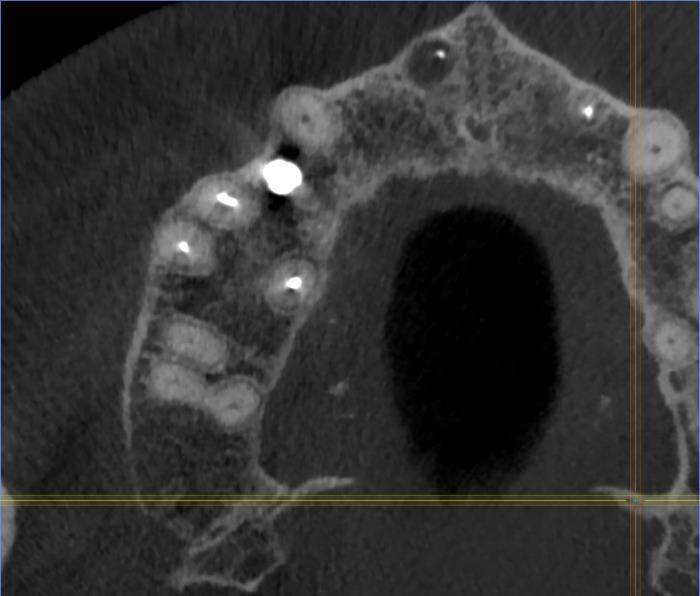

Есть зуб 11 (с СВШ) с восспалением около корня. До брекетов тоже было.

Перед протезированием предлагают перелечить каналы через корень с извлечением СВШ и последующим восстановлением (не понятно правда с СВШ или уже без него. Без СВШ зуб прям под корень может обломаться) под коронку.

До этого предлагали резекцию. Как в итоге лучше, через корень или резекцию?11-2.jpg.ba542aa82cfd6ddaad3fb9e234b99d99.jpg11.jpg.a34f40916e8e638d622001c50fff6e3a.jpg11-3.jpg.7a281f5893f8e6440937071fda10d523.jpg11-4.jpg.6a62c56e00cfdfa00cf35b7e276fd908.jpg